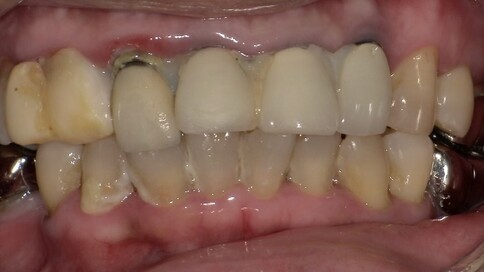

面對前牙(門牙)的缺損或美觀問題,我們通常會根據「修復範圍」與「牙齒健康狀況」,在全瓷冠與陶瓷貼片之間做選擇。

當您只有「單顆」門牙受損時,挑戰在於模仿隔壁那顆「天生的牙」。我們利用全瓷冠的高透光性創造視覺平衡,避免做出一顆看起來很新卻很突兀的假牙。